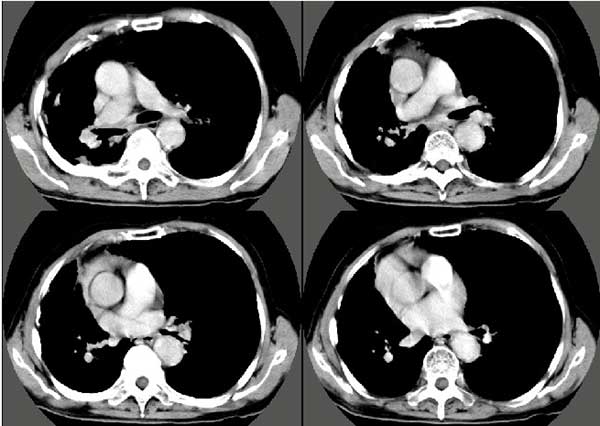

以下是引用扬仪在2005-5-12 20:46:40的发言:[br]右肺呈术后改变;双侧肺野散在分布斑片状、点状高密度病灶,(似可见“树芽征”);左上尖后段见斑团状高密度病灶(2个层面?),边缘毛糙,段性分布,与斜裂相邻,临近胸膜粘连;增强示病灶边缘强化,内呈水样密度;心影、纵隔右移,内可见4r淋巴结肿大。[br]意见:1、双肺继发性肺结核,左上为干酪病灶;[br] 2、矽肺合并感染;[br] 3、建议抗痨+抗炎。 [br]愚人之见,请高人指教!